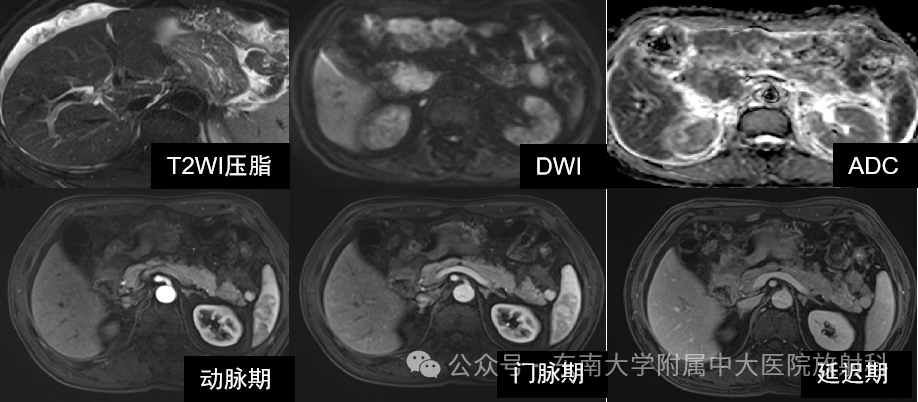

Glisson鞘水肿的影像诊断